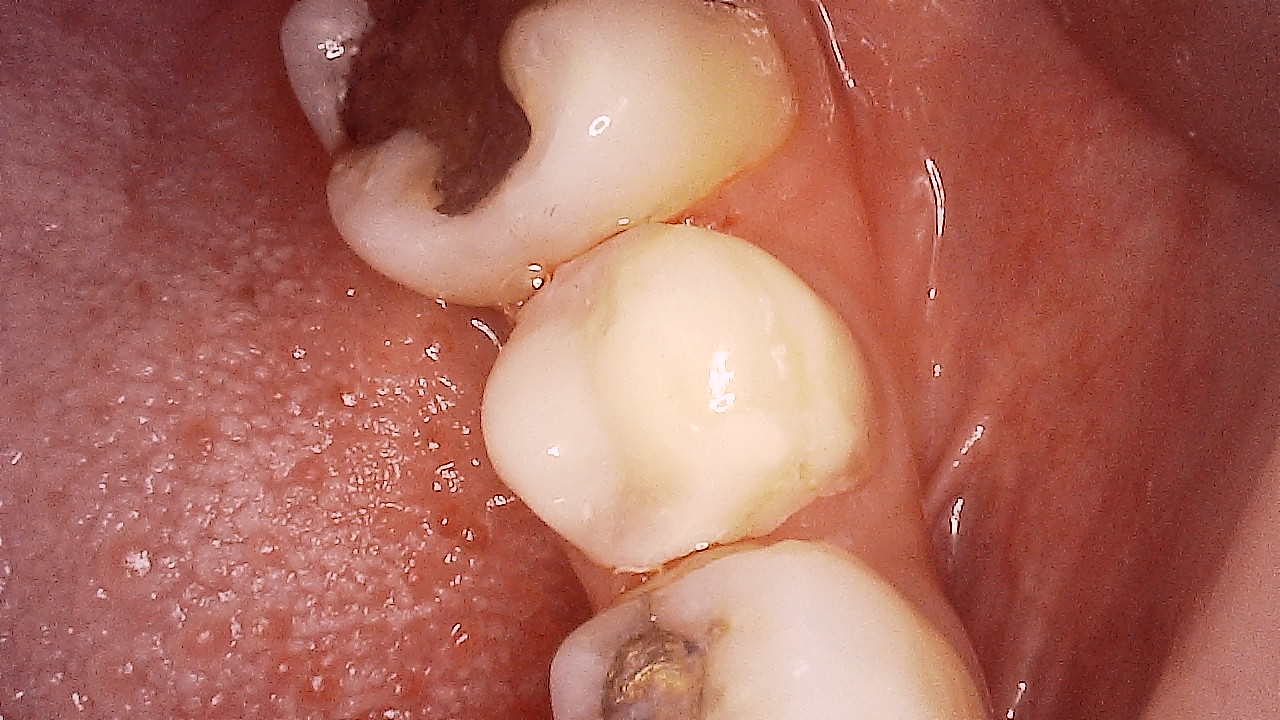

- 9/24/22 - Check up & Xray 10/01/22 - RCT 18mm , formacresol #35 10/08/22- RCT 17mm, campenol 10/15/22- 17.5MM PULP DEVITALIZER PAD done 11/05/22- Zirconia/LC 16 11/19/22- OP/Install Of Crowns